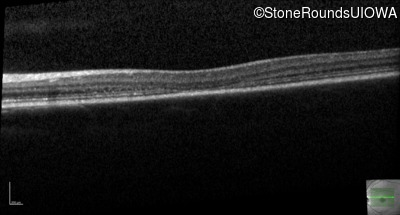

Optical Coherence Tomography - Left - 20/80 -1

Exemplar / OCT Stack